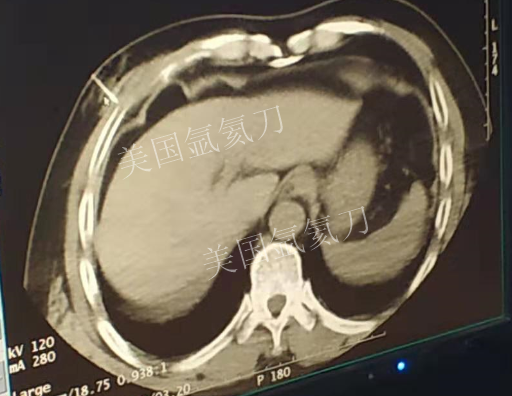

59岁男性肝部氩氦刀手术治疗

发布人:美国氩氦刀技术官方网站    发布时间:2019/3/13 15:42:57